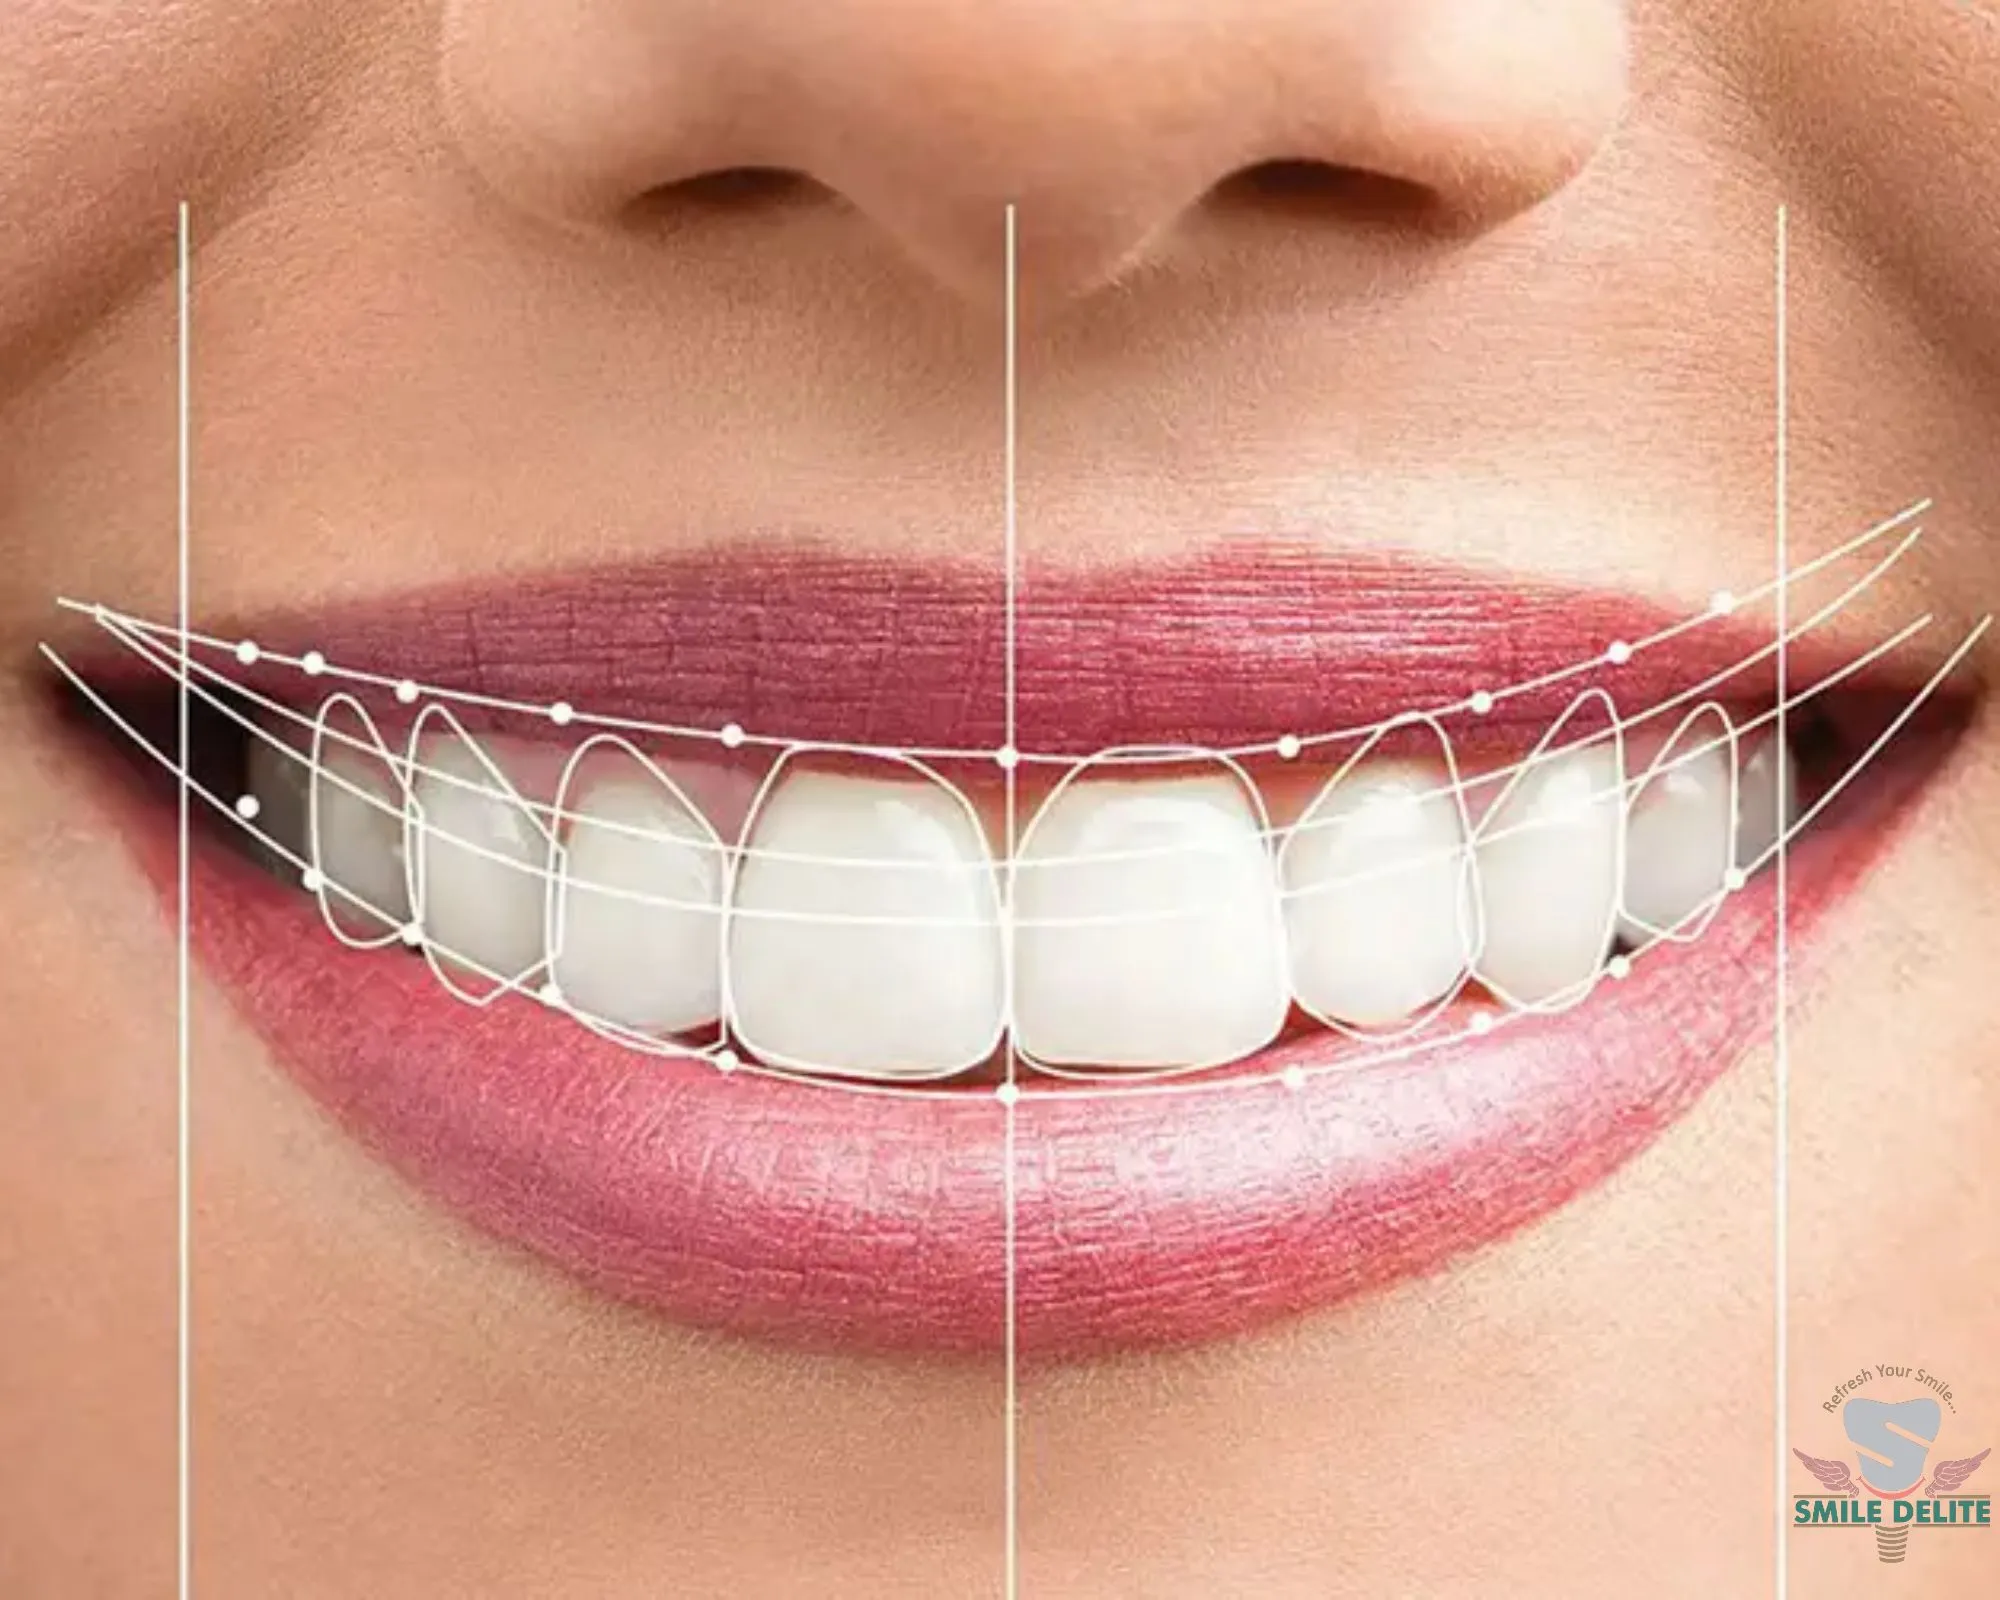

In-house digital imaging for accurate diagnosis and treatment planning.

Yes. SMILE D’ELITE has in-house OPG and CBCT imaging for accurate diagnosis and advanced treatment planning.